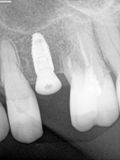

fredlibc | all galleries >> Galleries >> NSankhyan - immediate 13, impls 1121 and 25 with grafting > 25-2.jpg